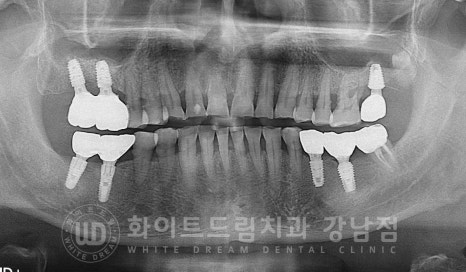

16, 17번 임플란트 치료와 함께

상실된 27번 치아 부위 임플란트 치료도 함께 진행하길 원하셔서

당일 임플란트 3개를 모두 식립하게 되었습니다.

▲ 흔들리는 어금니크라운 제거 후 임플란트 즉시 식립 : 24.03.02

환자분은 잇몸 염증으로 잇몸뼈의 소실이 심했기에

뼈이식이 동반되어야 하는 상태였는데요.

게다가 상악동이 아래쪽에 위치하고 있으신 분이었기에

16, 27번 임플란트 치료는 상악동 거상술을 동반하여 수술을 진행하게 되었습니다.